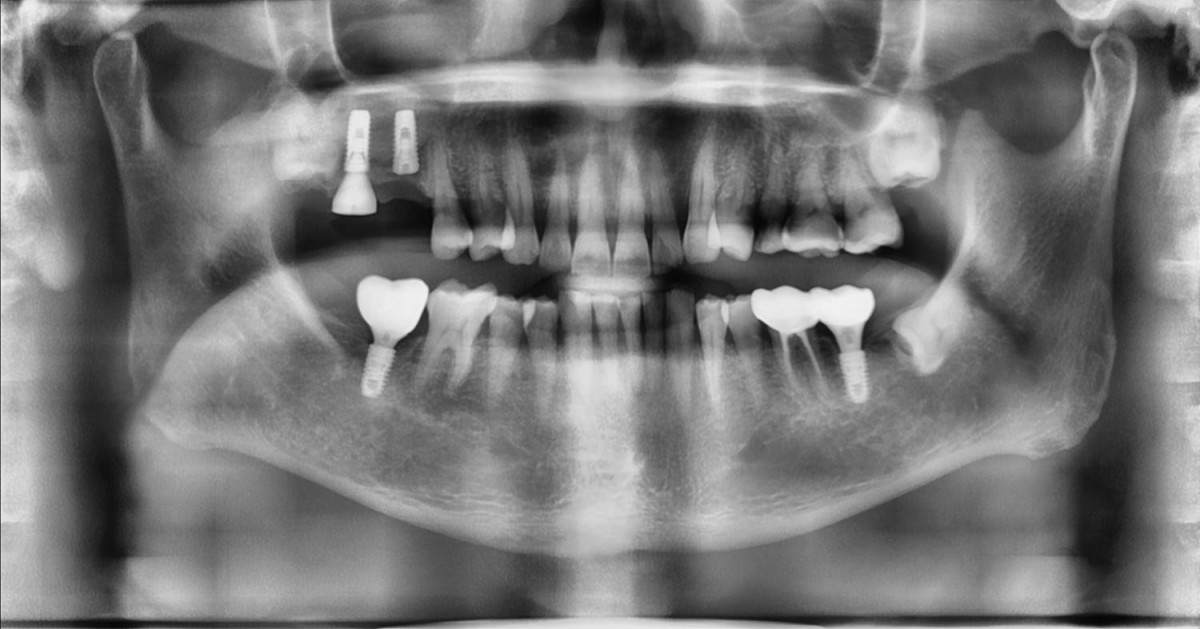

Maxillary Sinus Graft, 2 Implants, Crown Contouring

<GCaks> A 56-year-old male patient had pain-inducing caries, and perio-involved tooth mobility resulted in a tooth fracture at 1st molar. And it was removed months ago. He was a heavy smoker and showed poor oral hygiene.